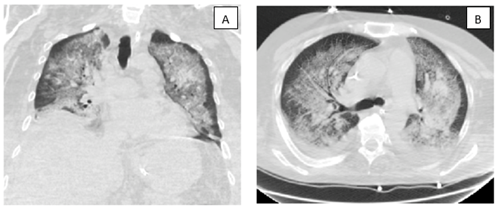

A 44-year-old male with a history of chronic alcohol use presented with a 7-day history of fever, myalgias, weakness, and progressive abdominal distention. On examination, he appeared icteric, with scleral icterus, left conjunctival suffusion, and ascites. Laboratory workup revealed severe hyponatremia (Na: 102 mEq/L), leukocytosis (WBC: 15.6 x10%L), and marked hyperbilirubinemia (total bilirubin: 16.5 mg/dL). A chest radiograph showed a patchy pneumonic process. Given his epidemiologic risk and clinical findings, leptospirosis was suspected. Empiric therapy with intravenous ceftriaxone and doxycycline was initiated, and Leptospira IgM testing was sent. Despite early antimicrobial treatment, the patient's condition deteriorated, requiring ICU transfer for septic shock management with vasopressors. Broad-spectrum antibiotics (vancomycin and piperacillin-tazobactam) were initiated. He subsequently developed worsening hypoxemic respiratory failure, necessitating mechanical ventilation. High-resolution CT of the chest demonstrated bilateral diffuse progression of multifocal ground-glass opacities, in the presence of worsening hemoptysis which is consistent with DAH (Figures 2 A / B). A bronchoalveolar lavage was subsequently performed, which confirmed the diagnosis. Ventilatory management included high PEEP, increased FiO2, and lung-protective tidal volumes. Adjunctive corticosteroid therapy was initiated. However, persistent bloody endotracheal secretions indicated ongoing alveolar bleeding, complicating ventilatory strategies. Prone positioning was employed as a salvage maneuver, but the patient's course was further complicated by multiorgan failure.

Figure 2 A / B: Chest CT scan demonstrating marked progression of multifocal confluent opacities, as can be seen in the setting of diffuse pulmonary hemorrhage.

This case underscores the rare but potentially catastrophic pulmonary manifestation of leptospirosis: diffuse alveolar hemorrhage (DAH). Although pulmonary involvement in leptospirosis is increasingly recognized, DAH remains an infrequent but severe complication associated with high mortality [1]. The underlying pathophysiology is believed to involve immune-mediated capillary injury, where leptospiral antigens trigger a cascade of inflammatory responses resulting in disruption of the alveolar-capillary barrier. This leads to extravasation of red blood cells into the alveolar spaces, culminating in hemorrhagic pulmonary infiltrates and hypoxemic respiratory failure. Diagnosis of DAH in the context of leptospirosis can be particularly challenging, as early clinical features are often nonspecific and mimic other infectious or inflammatory pulmonary syndromes [2,3]. Hemoptysis may be absent or minimal, further complicating timely recognition. Radiologic findings—such as bilateral ground-glass opacities or consolidations—are nonspecific and must be interpreted in conjunction with clinical suspicion and bronchoalveolar lavage findings demonstrating progressively hemorrhagic aliquots. Prompt recognition is critical, as rapid deterioration and progression to acute respiratory distress syndrome (ARDS) are common [1]. Mortality rates in leptospiral DAH can exceed 50%, particularly when diagnosis and escalation of care are delayed. Management is predominantly supportive, emphasizing lung-protective mechanical ventilation strategies to minimize ventilator-induced lung injury. Adjunctive therapies such as high-dose corticosteroids are frequently administered based on presumed immunopathogenesis, though robust evidence from controlled trials remains lacking [4]. In severe or refractory cases, additional interventions—including plasmapheresis, bronchial artery embolization, or extracorporeal membrane oxygenation (ECMO)—may be necessary to stabilize oxygenation and provide a bridge to recovery while hemorrhage control is achieved [6]. This case highlights the importance of maintaining a high index of suspicion for leptospiral DAH in endemic areas or in patients with appropriate exposure history, particularly when presenting with unexplained respiratory failure. Further research is urgently needed to better define optimal diagnostic and therapeutic approaches, as current management is largely extrapolated from case series and expert opinion.